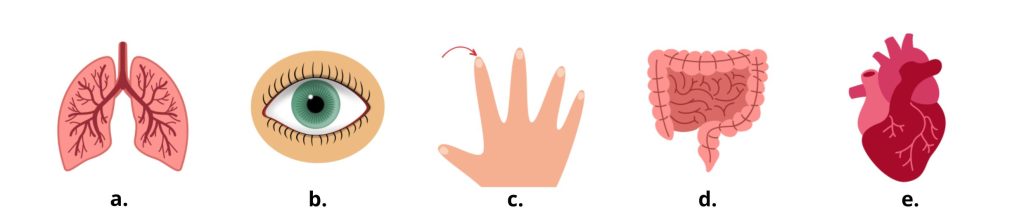

Les organes du corps humain en anglais 🫀

Il n’est parfois par suffisant de connaître seulement les parties du corps quand on va chez le médecin en anglais. En effet, il est possible que vous ayez mal à un de vos organes dans le corps. C’est pour cela que nous vous donnons une fiche de mots de vocabulaire des organes du corps humain en anglais :

➡️ Brain – cerveau

➡️ Heart – cœur

➡️ Lungs – poumons

➡️ Liver – foie

➡️ Kidneys – reins

➡️ Stomach – estomac

➡️ Intestines – intestins

➡️ Pancreas – pancréas

➡️ Bladder – vessie

➡️ Ovaries – ovaires

➡️ Cervix – col de l’utérus

➡️ Trachea – trachée

Faire correspondre le bon terme avec l’image

Trouver le mot adéquat en anglais pour chaque image ci dessous :